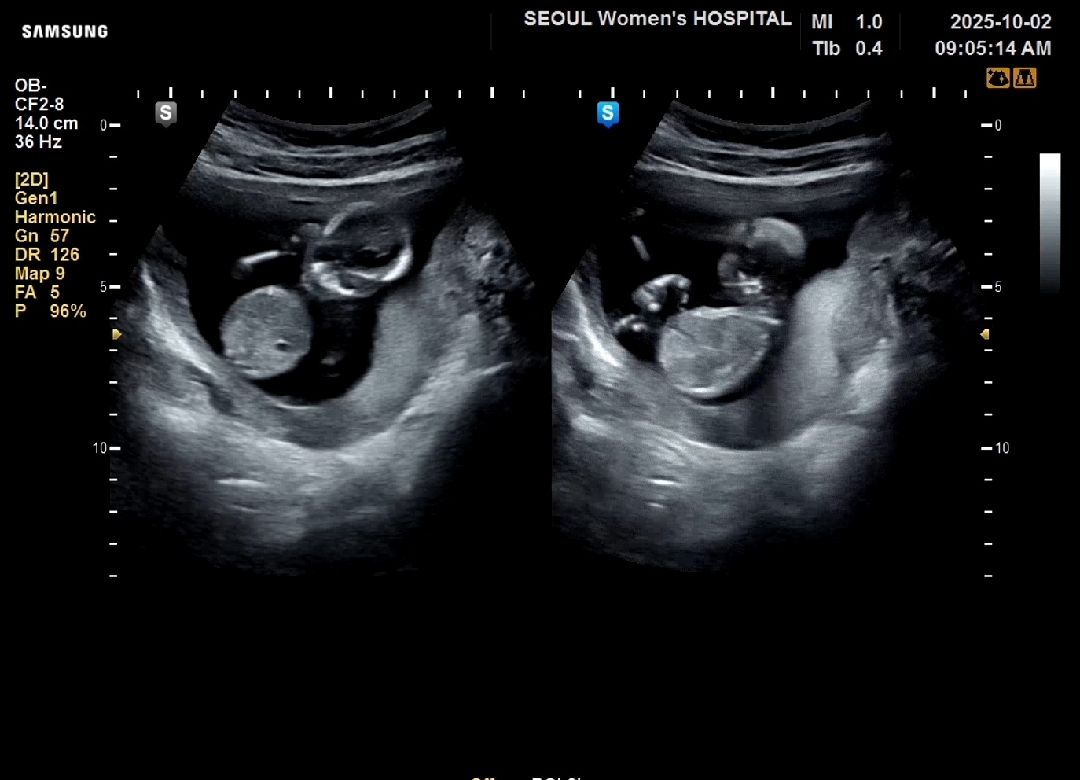

14주 성별 봐주세요🥰

딸일까요 아들일까요